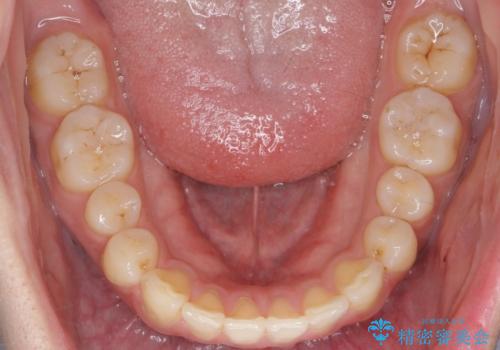

前歯が気になる。インビザラインライト

- 前歯が気になるとの事で来院。

矯正を希望されたが費用と時間を抑えたいとの事でインビザラインライトで矯正を行いました。(奥歯の位置関係はほぼ変えない)

前歯が綺麗に並び大変満足して頂けました。